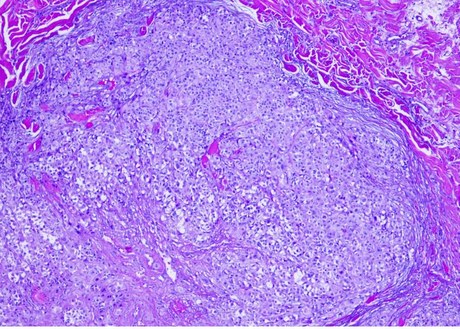

- Ocular melanomas represent approximately up to 5% of all melanomas in the United States (U.S.), with 85% of those reported to be uveal melanoma. Uveal melanoma is considered to be rare, with an estimated incidence of 2000 cases per year in the U.S.; however, it is associated with relatively high mortality secondary to metastasis.1-2

- An estimated 90% of these metastases are concentrated predominantly within the liver or are solely confined to it.